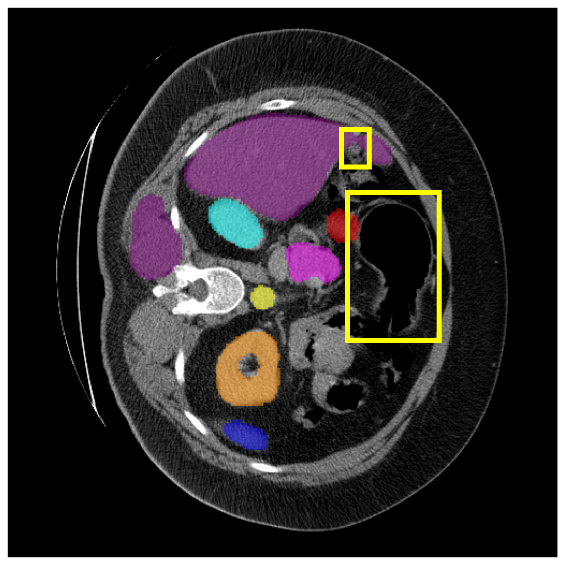

4.3.2 Visual Comparisons

Visualization of our method on the Synapse and ACDC datasets is shown in Fig. 3(a) and Fig. 3(b). For the Synapse dataset illustrated in Fig. 3(a), FCT failed to accurately segment SM and GB, while MERIT achieved precise segmentation of SM but struggled with GB. In contrast, our method achieved accurate segmentation of both SM and GB. Regarding the ACDC dataset shown in Fig. 3(b), while previous methods achieve comparable segmentation of the Myo and LV to the GT, they exhibit noticeable errors on the RV, including invasion into adjacent organs and misrecognition. On the other hand, our method accurately segments across all three structures Myo, LV, and RV, performing as precisely as the GT. We demonstrate the superiority of our method quantitatively and qualitatively.